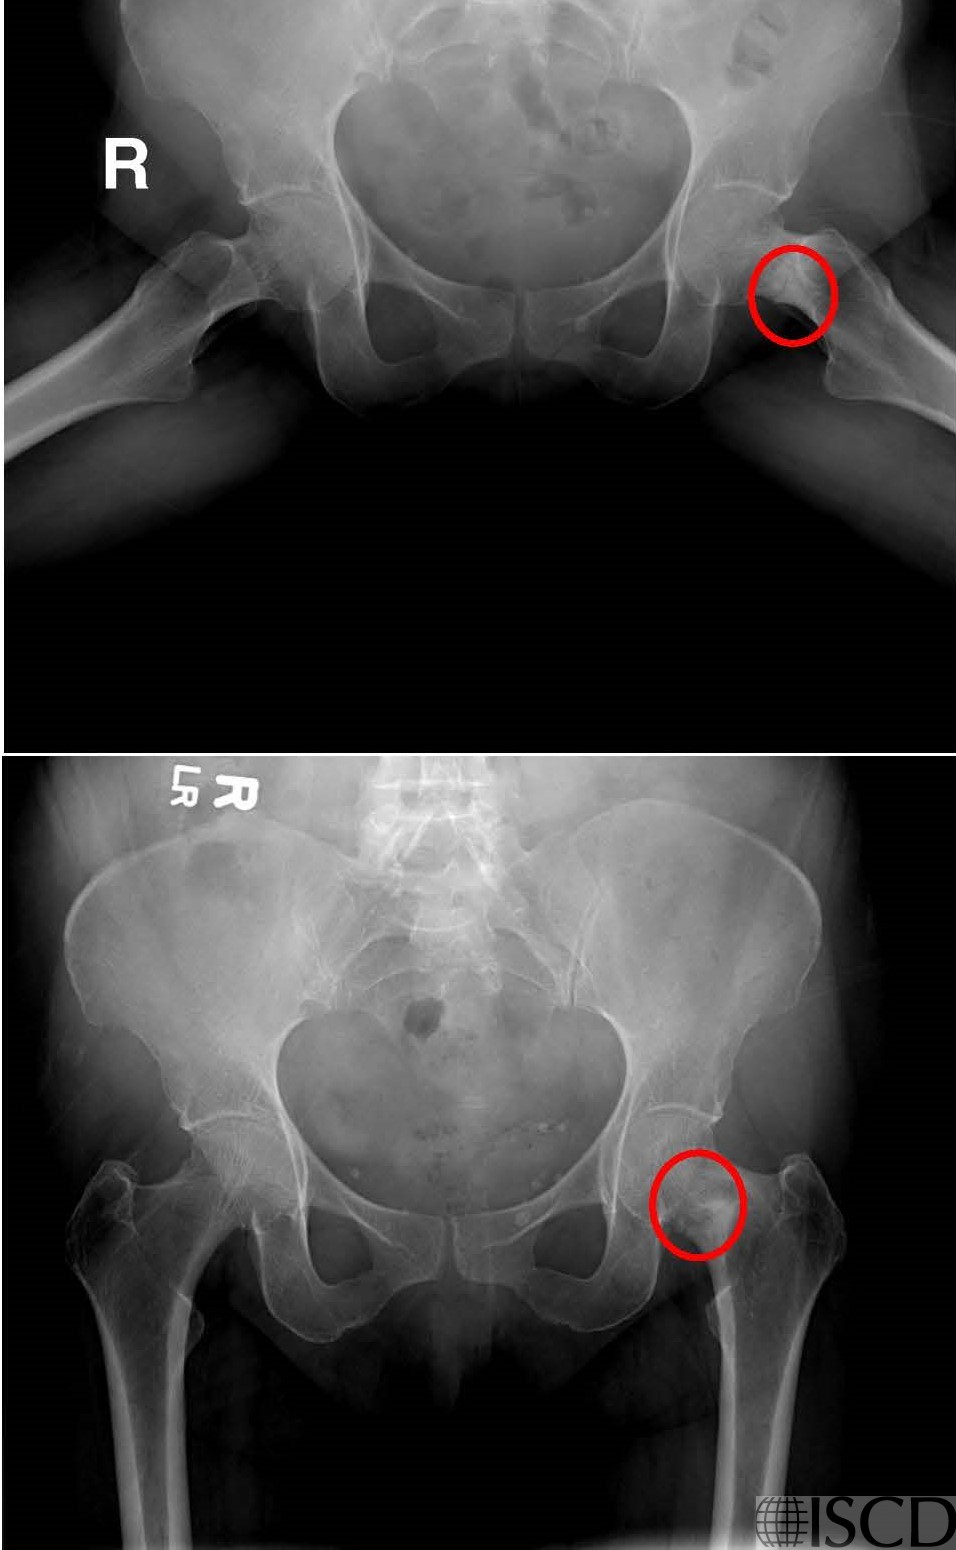

Femoral Neck Fracture

There is a linear opacity projecting upward into the left femoral neck. There is discordance in the bone mineral density between the femoral neck and total hip

On the radiographs, a fracture in the femoral neck is aparent (red circles).

On the Hologic left proximal hip image, there is a linear opacity projecting upward into the femoral neck. On the radiographs, a fracture in the femoral neck is seen. The patient was called and indicated that they were walking on the hip and were asymptomatic.